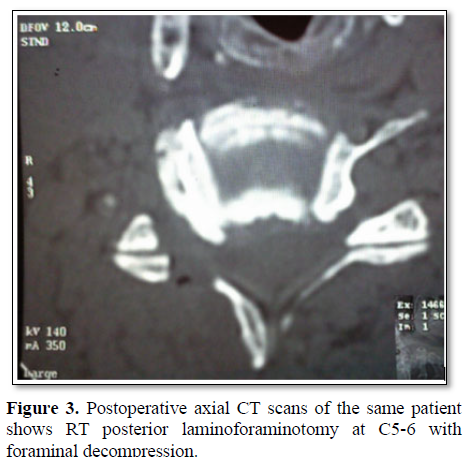

Cervical radiculopathy is a clinical diagnosis defined by the presence of sensory or motor deficits caused by mechanical compression of the corresponding cervical nerve root. Degenerative etiologies include disc herniation, spinal canal stenosis and spondylotic foraminal stenosis [1] (Figure 1). Cervical radiculopathy caused by posterolateral disc herniation can be managed by either an anterior or a posterior approach. The posterior approach was originally reported by Mixter and Barr [2]. The keyhole posterior foraminotomy was described by Spurling and Scoville [3].

The posterior laminoforaminotomy preserves cervical range of motion minimizes adjacent segment disease [4]. The conventional anterior cervical approaches use the surgical plane between medially trachea and laterally great vessels (carotid and jugular vein); and view the spine almost in face. These approaches can be called as anteromedial approach. On the other hand, anterolateral cervical foraminotomy approach retracts the great vessels medially, uses a more lateral angle of view, and views the spine obliquely [2,5-8] (Figures 2 and 3).